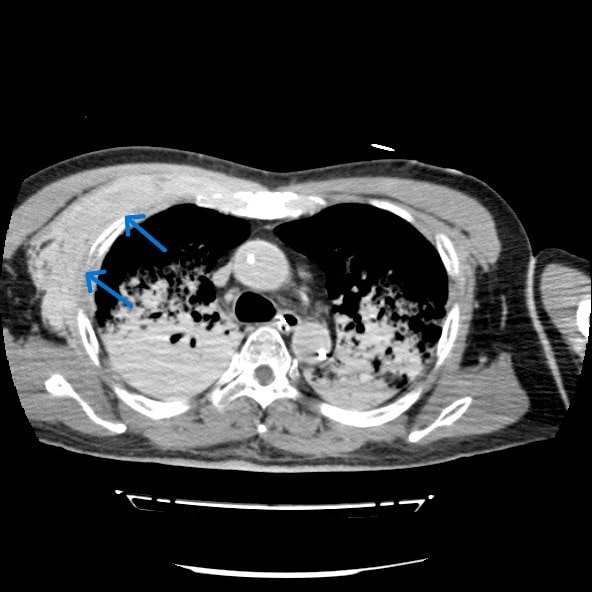

心筋梗塞によって心室細動をきたし心肺停止状態で当院に救急搬送された症例。救命活動が行われ心肺蘇生することができた。その後の経皮的冠動脈インターベンション(Percutaneous Coronary Intervention:PCI)の施行中に経皮的心肺補助法(Percutaneous Cardiopulmonary Support:PCPS)からの脱血不良あり循環血漿量減少が著明に進行していたため、原因精査目的に造影CTを撮影したところ、右第3肋骨周囲の前胸部に血管外漏出(extravasation)が認められた。

胸骨圧迫による動脈損傷が考えられたため、当院放射線科医師により緊急アンギオが施行された。右最上胸動脈および胸肩峰動脈からの出血が確認され、動脈塞栓術(TAE)にて止血することができた。

胸骨圧迫は心肺蘇生において不可欠な救命処置であるが、強い外力により外傷性合併症のリスクが存在する。代表的な合併症としては肋骨骨折や胸骨骨折の頻度が最も高く報告されており、血胸や胸壁血腫などの出血性合併症は報告により約10%程度とされている。ただし、出血源については明確ではなく、動脈損傷に関する症例報告は非常に稀である。特に内胸動脈や肋間動脈、最上胸動脈などの小血管損傷は画像検査が実施されなければ見逃される可能性が高く、臨床的にも認識されにくい。

本症例は、胸骨圧迫後に右最上胸動脈および胸肩峰動脈からの出血を認めた合併症例である。これまでの文献においても、胸骨圧迫後にこれらの動脈からの出血が明確に確認された症例はほとんど存在せず、本症例はその点で非常に特異性が高い。

本症例においては造影CTが循環不全の原因特定、胸骨圧迫による血管損傷の可視化、出血量評価、他臓器損傷のスクリーニングおよび治療方針の決定に有用であった。本症例のような稀な合併症を見逃さないためにも、胸骨圧迫後の症例では、一般的な骨折だけでなく、稀な血管損傷の可能性も念頭に置き、早期に造影CTによる精査を積極的に行うことが重要である。